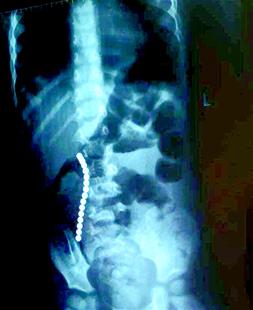

楚天都市報訊 圖為:手術(shù)取出的磁鐵球元元吞進(jìn)肚子里的一串磁鐵球

孩子胃腸里找出16顆珠子

武漢兒童醫(yī)院普外科病區(qū)專家閆學(xué)強介紹,他們從元元肚子里取出來的珠子直徑約為5mm左右,共計16顆,分別位于胃部和小腸部。閆學(xué)強說,這16顆珠子造成元元小腸上共計6處穿孔,胃后壁上也發(fā)現(xiàn)了一處穿孔。術(shù)中切除了元元近10cm長的小腸,并對其胃部穿孔進(jìn)行了修補。目前,元元的情況終于穩(wěn)定了。